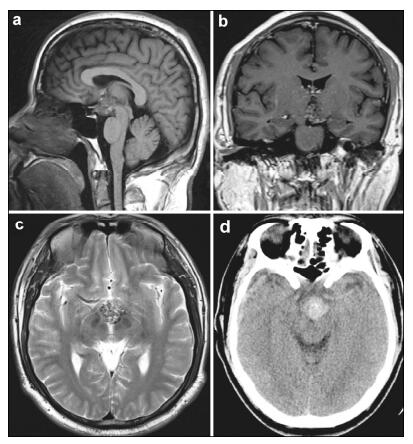

2 Case presentationA 40-year-old male, who complained of impaired vision in the left eye for a year and a half, was hospitalized for further examination of a suprasellar region mass detected at his local hospital. He was otherwise healthy and had no significant past medical history or history of trauma or surgery. Eye examination showed his best-corrected visual acuity was 0.8 in the left eye and no obvious abnormality in the right eye. He demonstrated no visual field defect or any other symptoms. No other neurological abnormalities were found. The pituitary hormonal examination and physical examination were normal. Computed tomography (CT) demonstrated a mass located in the suprasellar region. MRI on admission demonstrated a 2.2 mm × 2.5 mm × 2.1 mm regular-shaped round lesion located in the suprasellar cistern, to the rear of the optic chiasm. The lesion showed upward extension into the third ventricle. T1-and T2-weighted images showed mixed signal intensity with no edema around the lesion. A contrast-enhanced scan showed a hetero geneous mild enhancement (Figure 1).

| Figure 1 Magnetic resonance imaging (MRI) and computed tomo graphy (CT) of the presurgical hypothalamic cavernous malformation. (a) Sagittal section of T1-weighted MRI shows mixed-signal, round lesions located in the suprasellar cistern. (b) Coronal section of gadolinium-enhanced T1 images show a heterogeneous mild enhancement of the lesion located in hypothalamus. (c) Axial section of T2-weighted MRI shows the lesion’s upward extension into the third ventricle. There was no typical hypointense signal rim around the lesion. (d) Unenhanced computed tomographic imaging reveals a hyperdense lesion in the suprasellar region. |

Consequently, the patient was treated with micro surgical dissection via right pterional craniotomy. During the surgery, we confirmed that the lesion was located in the suprasellar region, broke upward into the third ventricle and downward into the inter peduncular cistern. The lesion was gray-red in color, soft but solid, covered by a membrane, and with a rich blood supply from the right posterior cerebral artery. The upper part of the lesion was embedded in the hypothalamus and caused slight compression of the optic chiasm and optic tract. We completely removed the lesion between the optic nerves and internal carotid artery. The pituitary stalk could not be protected completely because of the close adhesion and massive invasion of the lesion. All other peripheral tissues remained intact, including the brain paren chyma, anterior cerebral artery, basilar artery, posterior cerebral artery, optic nerve, optic chiasm, and oculo motor nerve. Pathological examination confirmed that the surgical specimen was CM (Figure 2).